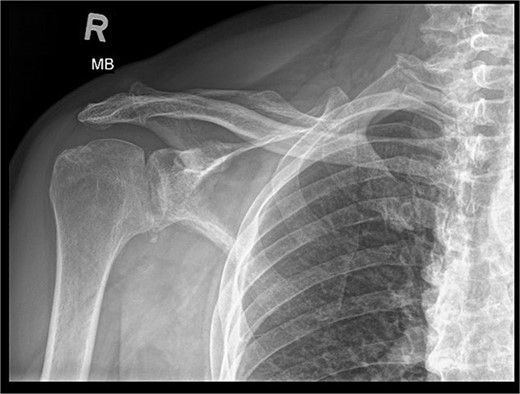

During the outpatient follow-up visit at the Orthopedic Clinic, ~10 weeks after the accident, a physical examination of the patient was conducted, which included shoulder X-ray imaging. The examination revealed severe pain in the right shoulder and a significant limitation in the mobility of the joint (results summarized in Table 1). The above enforced the decision of expanding the imaging diagnostics to look for fractures within the humeral head; hence, computed tomography (CT) and magnetic resonance imaging (MRI) examinations of the right shoulder were carried out. Additional imaging studies revealed a depression fracture of the humeral head covering 2/3 of the articular surface with posterior subluxation of the right shoulder joint. The examination also revealed that the continuity of the tendons of the rotator cuff muscles has been preserved.

MRI images can be found in Figs 3 and 4, and CT images in Fig. 5.